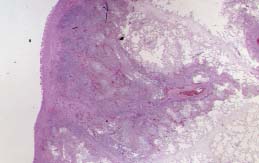

El 3er. patrón (Fig.11) es considerado intermedio en el espectro entre colonizacion e invasión. Es una forma progresiva, localmente destructiva. su aparición se halla favorecida por la existencia previa de EPOC, Sarcoidosis, Neumoconiosis; etc. Es una rara forma de presentación, que puede manifestarse (8) como : 1) Neumonía granulomatosa necrotizante (Fig.12), centrado por una zona de necrosis de coagulación resultante de la forma angioinvasiva; 2) Cavidad bronquial dilatada con inflamación granulomatosa y una "pelota de hongos" en su interior, con prolongaciones necrótico-inflamatorias a través de la pared de la cavidad; y 3) apariencia de granulomatosis broncocéntrica con bronquitis granulomatosa y bronquiolitis asociada a restos necróticos intraluminales, con reacción granulomatosa en empalizada sustituyendo a la mucosa. La invasión vascular suele estar ausente.

12p.jpg (11004 bytes)

Fig.12